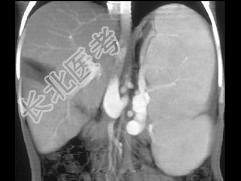

- 单项选择题患者肝移植术后1月,结合图像, 最可能的诊断为 ( )

A、肝脓肿

B、正常术后表现

C、肝梗死

D、血肿

E、以上都不是